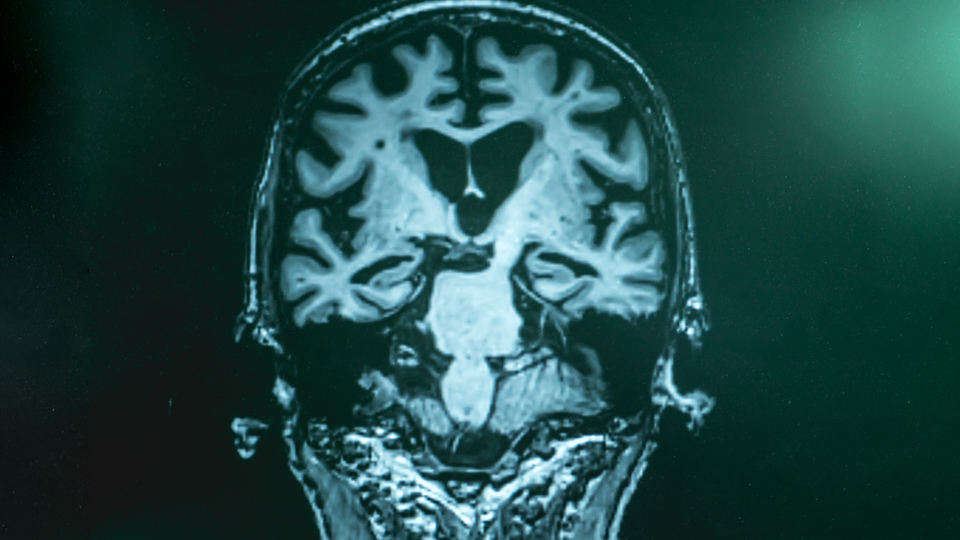

Onlarca yıllık araştırmadan sonra, artık Alzheimer hastalığına bağlı hafıza problemlerinin, beyinde sessizce gelişen dejeneratif süreçlerin bir sonucu olduğunu biliyoruz. Dejeneratif süreçte önemli rol oynayan vücudumuza aldığımız toksin birikimi ve kontrolsüz şeker düzeyleridir. Bu süreçler, beyindeki amiloid ve tau proteinlerinin anormal birikiminden kaynaklanır ve bu protein kümeleri, Alzheimer hastalığının tanımlayıcı patolojik özellikleridir. İlk zamanlarda bu protein kümeleri ancak ölen hastaların beyinlerinde otopside tespit edilebiliyordu. Daha sonra, beyin görüntüleme yöntemleriyle amiloid ve tau birikiminin tespiti sağlanmaya başlandı. Şu anda, Alzheimer'ın teşhisi için artık, pozitron emisyon tomografi (PET) taramaları ve omurilik sıvısından alınan örneklerle amiloid ve tau proteinleri ölçülerek bir değerlendirme yapılıyor. Ancak, PET görüntüleme oldukça maliyetli ve radyoaktif madde içeriyor. Omurilik sıvısı testleri ise invaziv, karmaşık ve zaman alıcıdır.